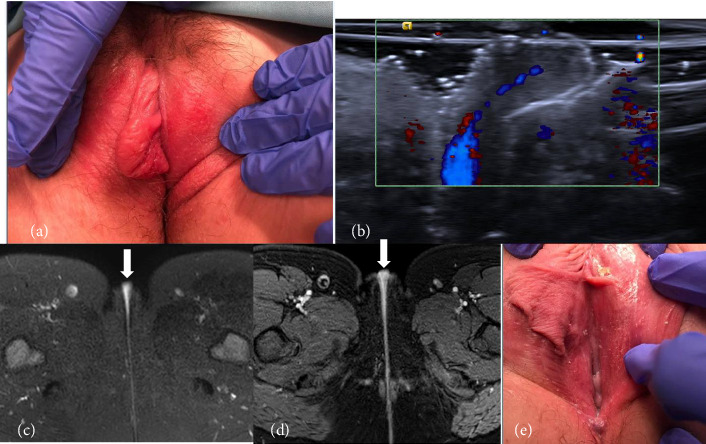

背景:文献描述青少年阴唇的放射影像缺乏,可能导致误诊和不必要的医疗护理。病例:两名青少年患者表现为突发性单侧小阴唇增大,并进行了多次影像学检查,发现了一个离散的肿块。一名患者在急诊室长时间住院后被诊断为口腔溃疡,另一名患者在麻醉下接受肿块切除检查,发现小阴唇卷曲。结论:由于缺乏关于预期结果的文献,青少年小阴唇肿大可能在放射成像上被误认为是一个离散的肿块。临床相关性和了解年龄相适应的病因的非感染性唇肿是至关重要的,以避免不必要的医疗治疗和程序。

Background: Literature describing radiologic imaging of the adolescent labia is lacking and may lead to misdiagnoses and unnecessary medical care. Cases: Two adolescent patients presented with sudden-onset unilateral labia minora enlargement and underwent multiple imaging modalities which identified a discrete mass. One patient was diagnosed with aphthous ulcers after a prolonged emergency department stay, and the other underwent an exam under anesthesia for mass removal and was found to have an elongated labia minora rolled into itself. Conclusion: Labia minora enlargement in adolescents can be significant and may be mistaken for a discrete mass on radiologic imaging given a lack of literature on expected findings. Clinical correlation and understanding of age-appropriate etiologies of noninfectious labial swelling is crucial to avoid unnecessary medical therapies and procedures.